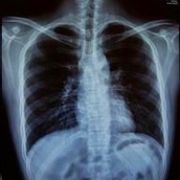

胸片是什么

胸片就是普通x线胸部平片,一般都是拍胸部正位片。胸部正位片主要显示的是两侧的肺野,心影轮廓大小,胸椎,以及肋骨。作为影像科普通的检查,方便、快捷,为临床科室解决了许多常见的问题。比如...